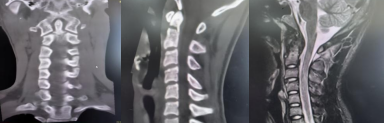

患者杨某因摔伤出现颈背部疼痛、活动受限,于受伤1小时余急诊入院。经影像学检查及专科评估,确诊为“颈枢椎齿状突基底骨折”。该骨折部位具有较高风险——枢椎齿状突紧邻延髓(生命中枢相关结构),若发生骨折移位,可能压迫延髓引发危急情况,需尽快制定安全的治疗方案。 ▲术前CT及MRI 针对患者的病情,脊柱外科主任柯绍强第一时间组织科室核心成员开展病例讨论。结合患者年龄特点,团队最终确定采用“经皮前路枢椎齿状突骨折切开复位空心钉内固定微创手术”。该术式虽具有出血少、创伤小、术后恢复周期相对较短的特点,但操作难度较高:颈枢椎周围分布食道、气管、颈总动静脉等重要解剖结构,且需固定的枢椎齿状突体积较小,穿刺针的角度、深度若出现偏差,可能损伤周边重要神经血管,存在一定风险。 为保障手术安全,脊柱外科团队术前反复推演手术流程、完善应急预案,并邀请中山大学孙逸仙纪念医院脊柱外科专家唐勇教授到场指导。手术过程中,医护团队密切配合,精准操作,成功避开周围重要组织,顺利完成骨折复位与内固定操作,术中患者生命体征保持平稳。 术后检查显示,患者四肢功能未出现异常,无发生相关并发症。术后第一天,患者在佩戴颈托的情况下可下床活动;术后7天经综合评估符合出院标准,予以办理出院手续。 ▲术后DR及CT ▲手术切口 医生提醒 颈椎是人体重要的支撑部位,青少年活泼好动,日常运动或意外摔倒时需注意保护颈部。若出现颈部疼痛、活动困难等情况,切勿自行按摩或随意转动头部,应立即就医检查,避免因延误治疗导致病情加重。 此次案例也提示,面对颈椎损伤等复杂伤情,需通过专业评估制定科学方案,规范的诊疗流程和团队协作是保障治疗效果的关键。 脊柱外科 基本概况 我院脊柱外科是阳江市“十四五”临床重点建设专科,开放床位35张,专注脊柱疾病临床研究与治疗。科室拥有16名专业医护人员,并与省内知名三甲医院建立长期合作关系,定期开展学术交流与远程会诊,确保患者在阳春本地就能享受到省级优质的脊柱疾病诊疗服务。 诊疗技术 科室配备超声骨密度仪、C臂X光机、德国Maroresn脊柱内窥镜等尖端设备,为精准诊疗提供坚实技术保障。 科室可独立开展六大核心技术: ▷上颈椎骨折脱位椎弓根钉内固定术 ▷颈椎前后路联合入路复杂手术 ▷多节段胸腰椎骨折修复术 ▷胸腰椎结核病灶清除+植骨融合术 ▷椎管肿瘤显微切除术 ▷退行性脊柱侧弯三维矫形术 微创技术是科室一大亮点,涵盖胸腰椎压缩性骨折经皮成形术、脊柱骨折微创内固定、椎间孔镜下椎间盘髓核摘除等前沿术式,以小创口实现大疗效,显著缩短患者康复周期。 科室坚持中西医并重,传承中医特色疗法,开展针灸、中药包外敷、穴位按摩、肢体康复锻炼等项目,为患者定制个性化综合治疗方案,让传统医学智慧赋能现代脊柱诊疗。 专家简介 唐 勇 医学博士,中山大学孙逸仙纪念医院脊柱外科副教授,硕士研究生导师,脊柱微创中心副主任。 专业特长:曾到美国加州大学脊柱中心留学进修。擅长脊柱外科研究,能熟练掌握脊柱外科高难度手术以及疑难病症的诊治。2010年开展世界首例单孔腔镜下腰椎前外侧手术治疗腰椎结核。2016年开展我国第一例达芬奇机器人脊柱手术。我国第一位获得达芬奇机器人操作许可证的骨科医生。 学术任职:担任中华医学会骨科分会微创学组全国委员、广东省医师协会脊柱内镜学组副组长。《脊柱内镜手术策略及操作图谱》主编。The International Journal of Neuroscience,The Journal of Rheumatology,Global spine journal 国际杂志审稿专家。 陆晓生 主任医师、党委副书记、院长、研究员、医学博士,硕士、博士研究生导师。 历任百色市妇幼保健院(副处)、百色市人民医院、北流市人民医院、新乡医学院第三附属医院(第三临床学院)院长(正处)。武汉大学硕士、广西医科大学博士毕业,深造于北京积水潭医院、匈牙利德布勒森大学等。 科研成果: 以第一作者发表专业论文20余篇(含SCI收录);获7项国家专利授权;主持科研项目获奖6项,其中1项获省部级科研立项资助和省部级科技进步奖,实现了百色市本级医疗系统在该领域的零突破。 学术任职: 现兼职任中国人体科技健康促进会现代医院精益管理专业委员会常委,曾兼任中国中西医结合学会骨伤科分会第八届委员会骨搬移治疗糖尿病足及微血管网再生专家工作委员会常委、广西医师协会骨科医师分会外固定专业委员会副主任委员、广西医院协会县级医院管理分会副主任委员、广西医师协会第一届创面修复与再生专业委员会副主任委员等专业学术职务。 荣誉奖项: 广西第一批高层次人才E层次、广西“十百千”第二层次人选、广西先进工作者(广西五一劳动奖章)等;百色市第七、八批专业技术拔尖人才;玉林市高层次人才第三、第四层次人选;荣获第六届“县域医疗榜样力量”系列评选奖优秀院长奖。 擅长领域: 熟悉骨科专业,擅长骨关节、创伤、脊柱基础和临床研究及骨科新器械研发及应用研究。对医院管理有丰富经验。 柯绍强 骨外科主任医师,脊柱外科主任。 毕业于广东医科大学临床医学专业,曾先后到广东省人民医院、中山大学附属医院脊柱外科及脊柱微创中心进修学习。曾发表多篇省及国家级医学论文,主持完成阳江市科研项目2项,广东省医学教育协会脊柱专业委员会常务委员、广东省基层医药学会脊柱专业委员会常务委员、广东省健康管理学会脊柱专业委员会委员、广东省康复医学会脊柱脊髓分会理事、阳江市医学会骨科分会副主任委员、阳江市医学会脊柱专业委员会常务委员。 擅长领域:熟练掌握脊柱外科高难度手术,率先在阳江地区开展经皮椎体成形术、经皮椎弓根钉内固定术、微创通道下腰椎融合内固定术及经椎间孔镜下椎间盘髓核摘除椎管减压等脊柱微创手术。擅长颈椎病、颈腰椎间盘突出、腰椎管狭窄、腰椎滑脱、胸腰椎骨质疏松性压缩性骨折、脊柱感染脊柱结核、脊柱脊髓损伤、脊柱畸形、脊柱肿瘤等疾病的诊治以及脊柱微创手术。 刘丙科 骨外科副主任医师,脊柱外科副主任。 毕业于广东医科大学,曾先后到中山大学附属第一医院脊柱外科、中山大学附属孙逸仙纪念医院脊柱微创中心进修学习。发表专业论文7篇,主持完成阳江市科研立项2项。广东省医院协会脊柱外科专业委员会第一届委员、广东省健康管理学会脊柱专业委员会第一届青年委员会、广东省基础医药学会骨科修复重建专业委员会第一届委员、广东省中西医结合学会骨科微创专业委员会第三届委员会委员、广东省医疗行业协会脊柱外科管理分会委员、广东精准医学应用学会脊柱脊髓病分会第一届委员、阳江市医学会脊柱外科学分会第一届委员会委员。 擅长领域:对脊柱各类疑难疾病诊治有丰富的临床经验,擅长颈胸腰椎管减压、椎间盘切除、椎体滑脱或骨折复位、椎间植骨融合、椎体病灶清除、椎弓根螺钉内固定术等传统手术,并擅长经皮椎体成形术(PVP)、经皮椎体后凸成形术(PKP)、选择性神经根阻滞术、脊柱内镜辅助下髓核摘除术、射频消融术等微创技术。 洪锦向 骨外科副主任医师。 毕业于广东医科大学临床医学专业,从事骨科工作10多年,曾先后到广州医科大学附属二院、广州医科大学附属一院骨外科进修学习。曾发表省及国家级论文7篇。 擅长领域:熟练掌握脊柱疾病、关节疾病、骨病、四肢骨折、创伤等常见病及疑难病的诊治,尤擅长脊柱各类疾病诊治及手术治疗。 胡海生 骨外科主治医师,脊柱外科硕士研究生。 研究生期间于南方战区总医院(原广州军区总医院)跟随马向阳教授、夏虹院长、吴增晖副院长等国内知名脊柱外科教授学习三年。曾在国内及国外杂志发表学术论文5篇,研究生毕业后主要从事脊柱外科临床工作。 擅长领域:对颈椎病、颈椎管狭窄症、寰枢椎脱位、脊髓损伤、脊柱骨折、腰椎间盘突出症、腰椎滑脱症、腰椎管狭窄症、骨质疏松性椎体压缩性骨折等脊柱疾病的诊断与治疗有较深入研究。